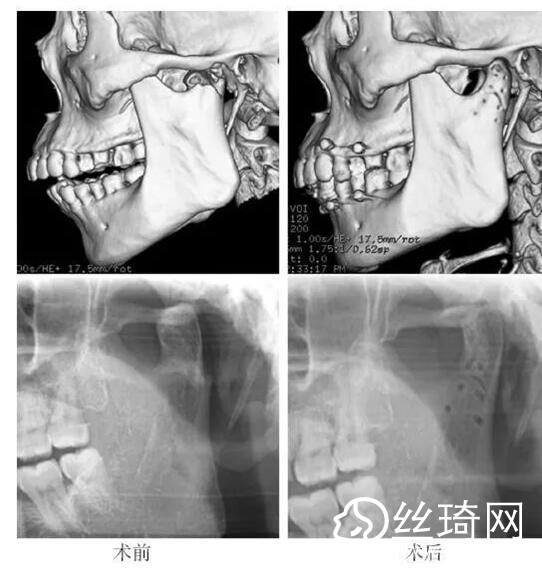

在106側(cè)中,髁突高位矢狀骨折46側(cè),中位髁頸骨折26側(cè),低位髁頸下骨折34側(cè)。髁突高位矢狀骨折及中位髁頸骨折均經(jīng)耳屏前徑路復(fù)位;34側(cè)低位髁頸下骨折中,經(jīng)耳屏前徑路復(fù)位13側(cè),頜下徑路復(fù)位19側(cè),頜后徑路復(fù)位1側(cè),穿腮腺徑路復(fù)位1側(cè)。髁突高位矢狀骨折復(fù)位后以1~2枚可吸收長螺釘固定(圖1)[3],采用的可吸收內(nèi)固定系統(tǒng)為BioSorb(ConMed Linvatec,芬蘭)、Inion OTPS(Inion,芬蘭);規(guī)格:直徑2 mm,長度15~20 mm。中位髁頸骨折及低位髁頸下骨折多以2塊可吸收板固定(圖2)[3],個別病例以1塊或3塊可吸收板固定,采用的可吸收內(nèi)固定系統(tǒng)為BioSorb(ConMed Linvatec,芬蘭)、Grand Fix(Gunze,日本)、Inion OTPS(Inion,芬蘭);規(guī)格:直4孔板,孔徑 mm或2.5 mm,長度21~35 mm,螺釘直徑 mm或2.5 mm,長度7~10 mm。可吸收釘板的手術(shù)操作采用專用器械工具盒,并遵照廠家操作指引進(jìn)行。

82例髁突骨折患者,術(shù)后隨訪6個月至3年,平均年。所有患者術(shù)后未訴明X不適,面型基本對稱,面部肌肉運(yùn)動正常,咬合對位良好,開口度~4.2 cm,平均(±)cm。3例患者開口型輕度偏斜,均為髁突高位骨折,其中2例為粉碎性骨折行骨折碎片摘除,1例為矢狀骨折,以可吸收螺釘固定后,創(chuàng)口感染,隨后行局部清創(chuàng)并取出髁突骨折片及可吸收螺釘,創(chuàng)口愈合良好。96側(cè)髁突骨折中,2例髁頸下骨折術(shù)后復(fù)查CT顯示輕度移位,但患者無功能障礙,持續(xù)觀察,未做特殊處理。其他患者未見明X排斥反應(yīng)及并發(fā)癥。